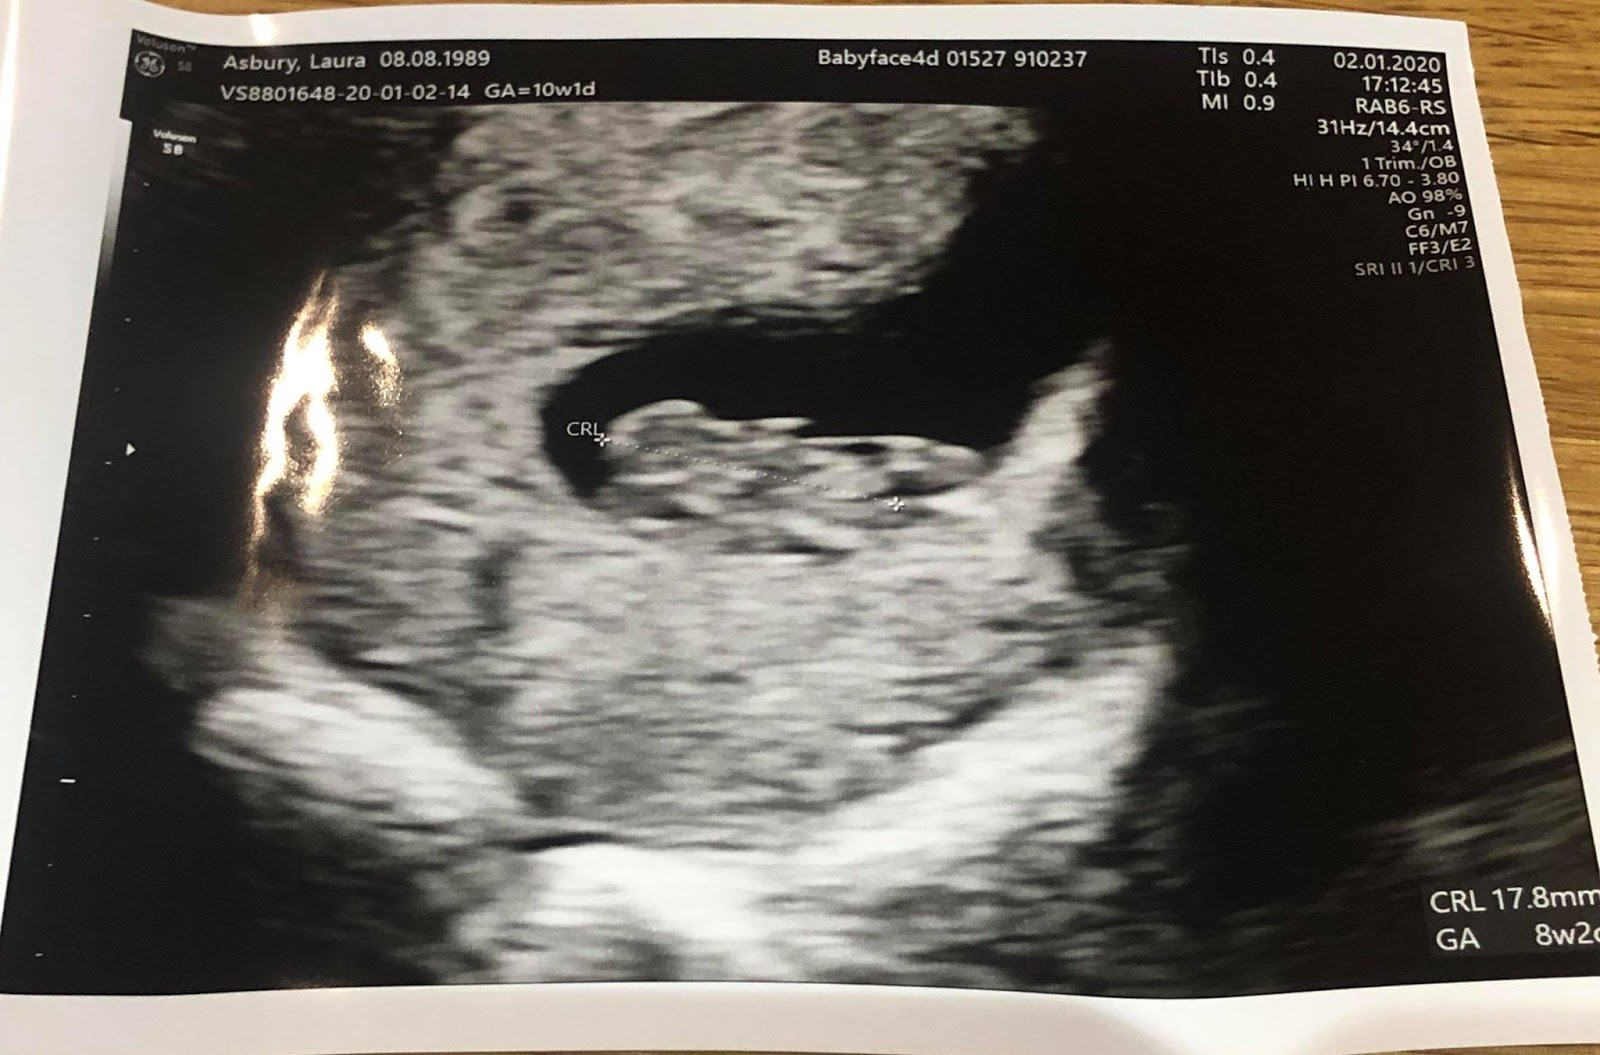

If you're not sure when you conceived, or, have had a previous miscarriage or pregnancy complications, an 8 - 10 week scan may be recommended . There's a lot which can be seen at 8 weeks gestation, including the baby's heartbeat and early development . It will also be possible to work out the baby's due date, which is why an 8 week ultrasound is often called a dating scan .

How is the scan performed? To obtain the best images possible, this scan is routinely performed internally and perfectly safe to perform during early pregnancy . What will I see on the ultrasound? At 7 weeks gestation a pregnancy sac should be seen within the uterus . Within this sac will be an embryo, heart motion and yolk sac should be visible . Approaching 8 weeks , early brain formation is identified with a black space in the head called the rhombencephalon .

A dating scan is usually done to check how many weeks' pregnant you are, but can be done for other reasons, such as if you have had bleeding during your pregnancy or you have had previous miscarriages . If you choose to have a dating scan , it will most probably be your first scan . You will need to get a referral from your doctor or midwife for a dating scan . Most women can instead have their first scan at 11 to 13 weeks β this is usually called the 12- week scan .

If you are going to have an early scan , 8 weeks is a good time to do it . If you see a baby with a HB measuring approx right for dates at that stage MC risk drops to 3% . At that stage they normally start with an abdominal scan but often need to do a vaginal scan to get accurate measurements .

Bleeding at 8 weeks pregnant . Anonymous . 29/08/2008 at 5:43 am . at eight weeks you will normally see a sack, a fetal pole and a heart beat . BUT . . .remember you could be a little earlier . I have had early scans with all three of mine, and by 8 weeks all three of the former were present . xx . 0 like .